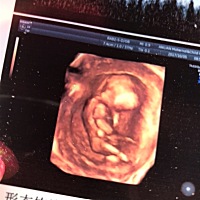

三个月,能看出来男孩女孩吗?

心率跳153次难道是女孩子?